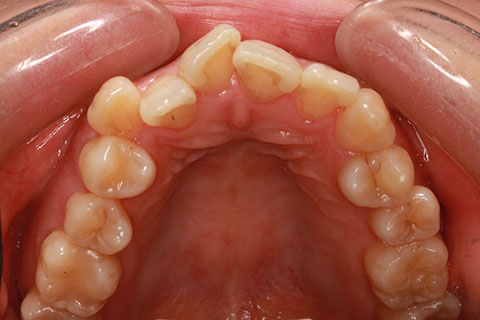

ハーフリンガル矯正3(上の歯のみ舌側矯正で治療)

治療前

治療中(開始直後)

治療中(開始半年後)

治療後

- 年齢・性別

- 25歳女性

- 治療期間

- 2年0ヶ月

- 抜歯

- 上下4番抜歯

- 治療費

- 110万円

- 備考

- 治療内容

- 施術の副作用(リスク)

- 表側矯正と比較して、力学的な操作性が複雑なため、ボーイングエフェクトを起こしやすい。